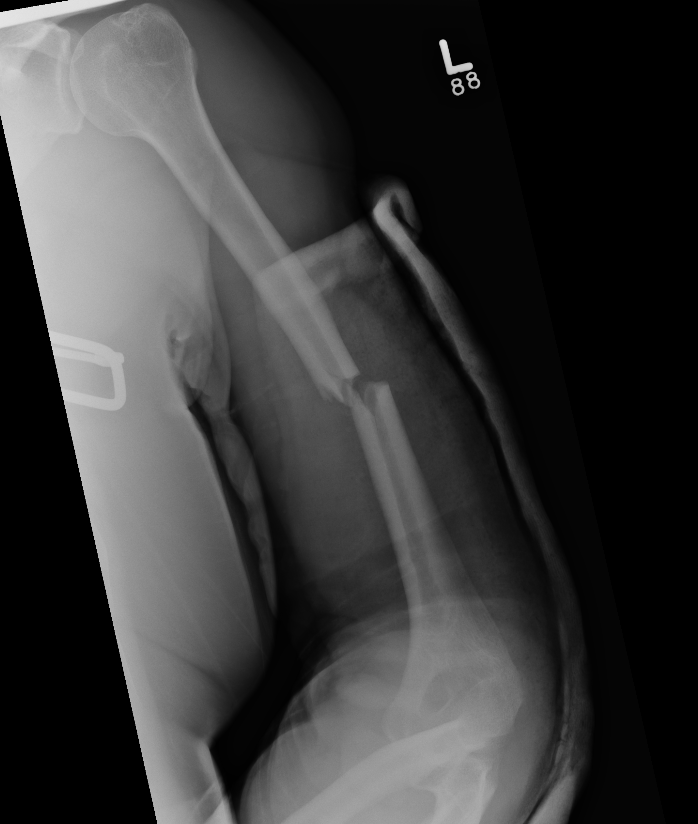

Displaced Humeral Fracture APDisplaced Humeral Fracture Lateral

Humeral Fracture SegmentalHumeral Plate LateralHumeral Plate Long AP

Segmental fracture ORIF